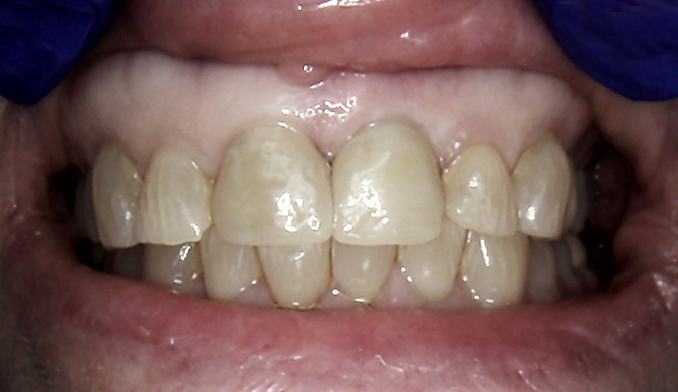

Restoration of Broken Front Bridge

The patient came in with a broken front bridge spanning three teeth. We were able to preserve the teeth supporting the bridge and created a custom new bridge to fit seamlessly, restoring both function and esthetics.